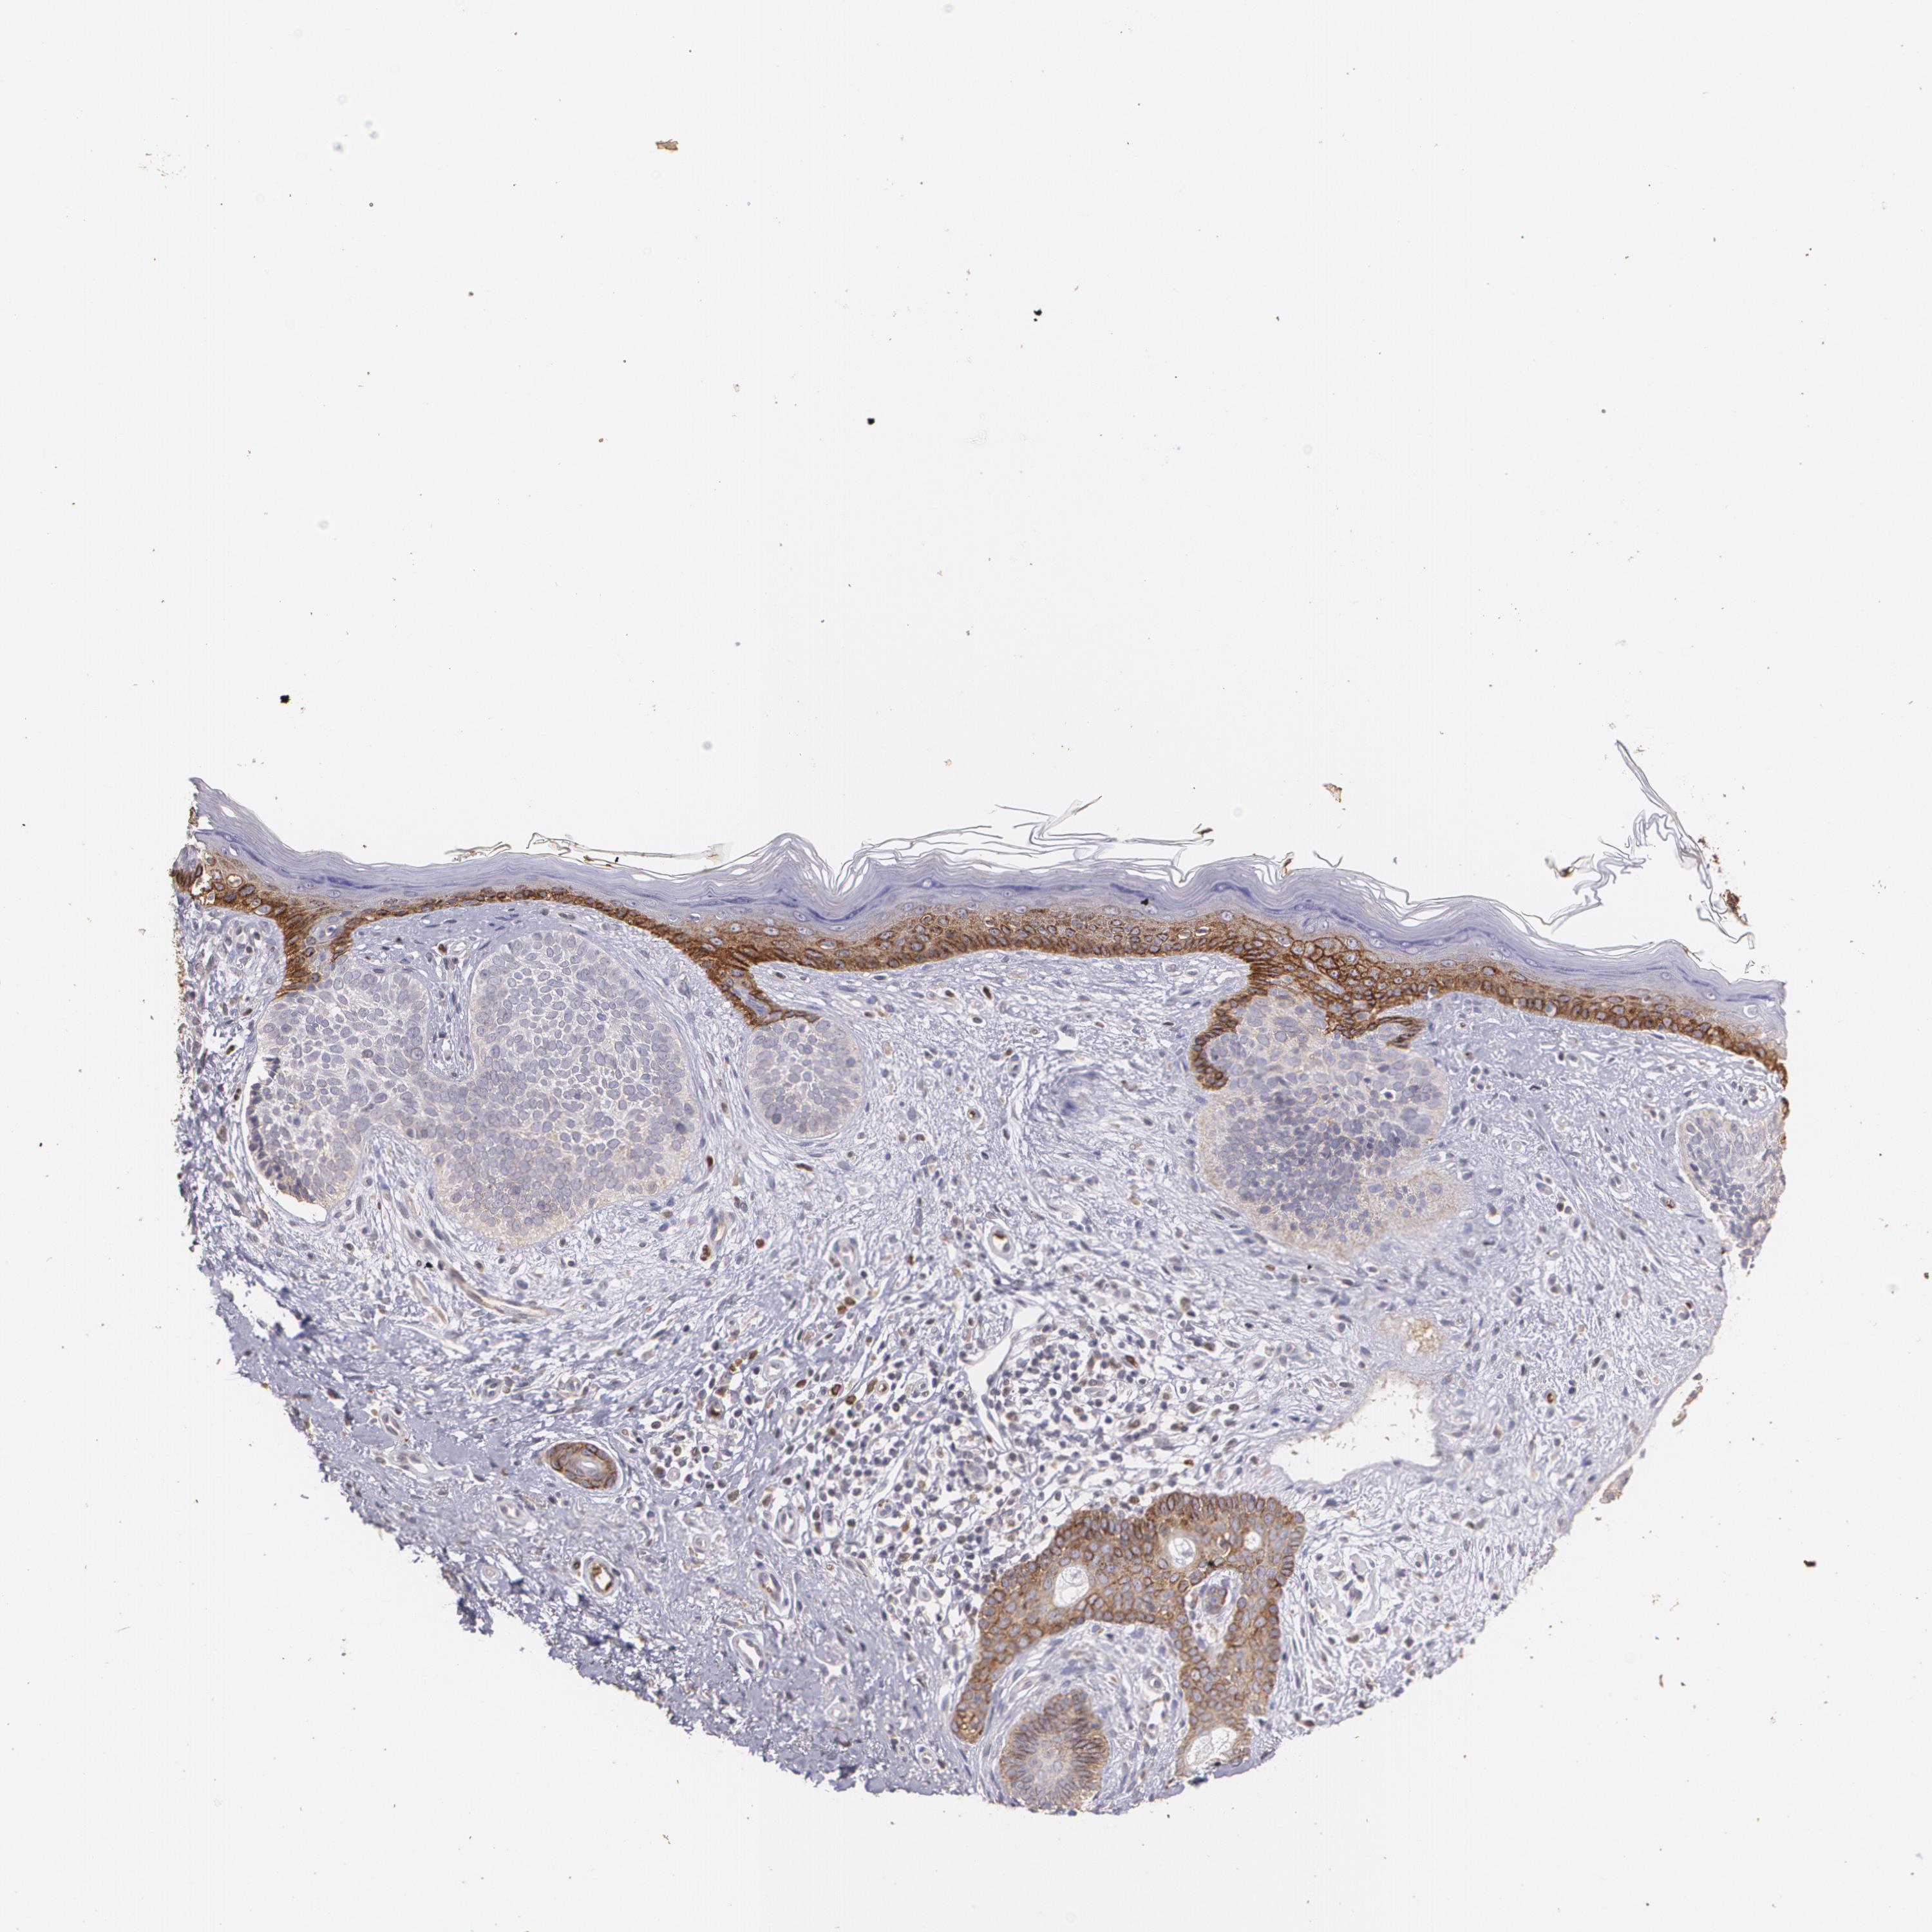

Basal cell and squamous cell cancer

SKIN CANCER - Protein expressioni

A mouse-over function shows sample information and annotation data. Click on an image to view it in a full screen mode. Samples can be filtered based on level of antibody staining by selecting one or several of the following categories: high, medium, low and not detected. The assay and annotation is described here.

Each image is clickable and will lead to virtual microscopy that enables deeper exploration of all samples and also displays staining intensity scores, fraction scores and subcellular localization as well as patient and tissue information for each sample.

Squamous cell carcinoma in situ, NOS

Squamous cell carcinoma, NOS